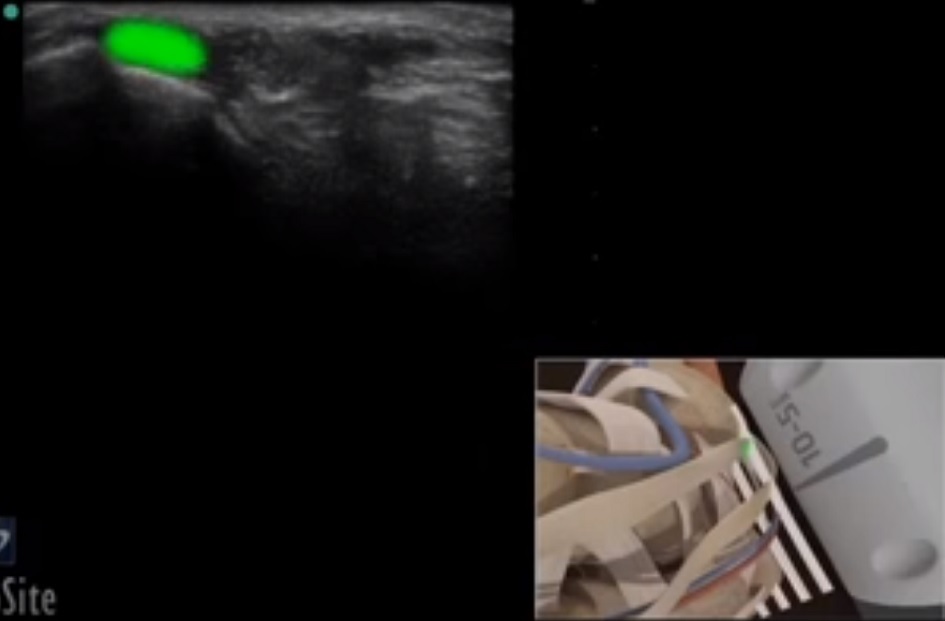

Bild: Fuß und Sprunggelenk, Sehne des Tibialis posterior

Markierter Bereich: Sehne des Tibialis posterior